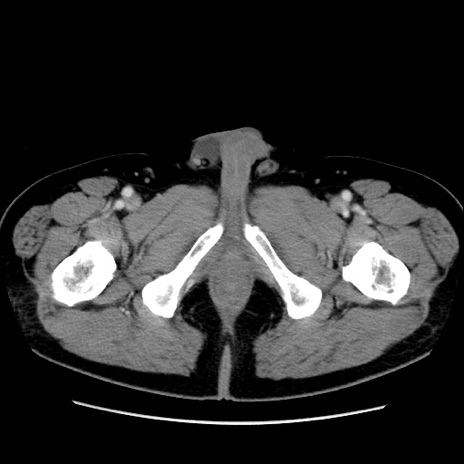

症例16(横断像)

【症例】 70歳代男性

【主訴】 腹痛、嘔吐

【現病歴】 約1ヶ月前より間欠的に腹痛と嘔吐あり、当院消化器内科を受診したところCTで多発する肝臓のLDAを指摘され、精査中であった。以降は消化器症状は安定していたが、2日前より嘔気と腹痛があり、同日より排便・排ガスが消失した。改善認めず、 本日、救急外来を受診した。

【既往歴】 大腸ポリープ切除後。

【身体所見】意識清明・会話良好、BT 36.3℃、BP 127/80mmHg、 P 80bpm、腹部:膨満あり、平坦・軟、上腹部正中および下腹部正中に圧痛あり、反跳痛なし、筋性防御なし。

【データ】WBC 7200、CRP 0.77